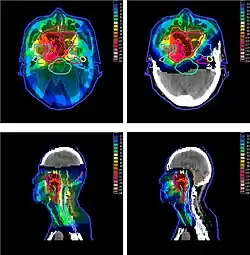

Главным преимуществом протонной терапии перед фотонной радиотерапией с модуляцией интенсивности (IMRT) является снижение побочных доз, получаемых здоровыми тканями, в особенности позади пика Брэгга. Таким образом, протонная терапия применяется чаще всего в случаях, когда опухоль расположена в тесном окружении жизнено важных органов (organs at risk — OAR): опухоли мозга, шеи, основания черепа. Также, предпочтение протонам часто отдаётся в случае лечения заболеваний у детей[32], поскольку большая ожидаемая продолжительность жизни и активно делящиеся клетки растущего организма требуют снижения побочных доз облучения[33].